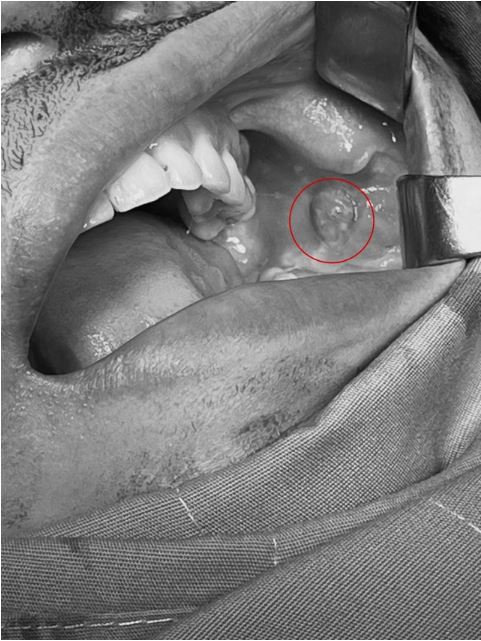

Qua thăm khám, bác sĩ nhận thấy có lỗ dò chảy mủ ở niêm mạc má trái tại vị trí thắt đồng tiền, sờ bên trong có khối cứng, hình ảnh siêu âm ghi nhận áp xe mô mềm má trái. Bệnh nhân được chẩn đoán viêm mạn tính, áp xe mô mềm má trái, có dị vật má trái, tiền sử làm má lúm đồng tiền 5 năm. Các bác sĩ đã tiến hành phẫu thuật rạch áp xe, cắt lọc, nạo mô viêm, bơm rửa, lấy dị vật là sợi chỉ ở vùng má. Ca phẫu thuật kéo dài khoảng 15 phút, người bệnh sau đó được theo dõi hậu phẫu và xuất viện ngay trong ngày.